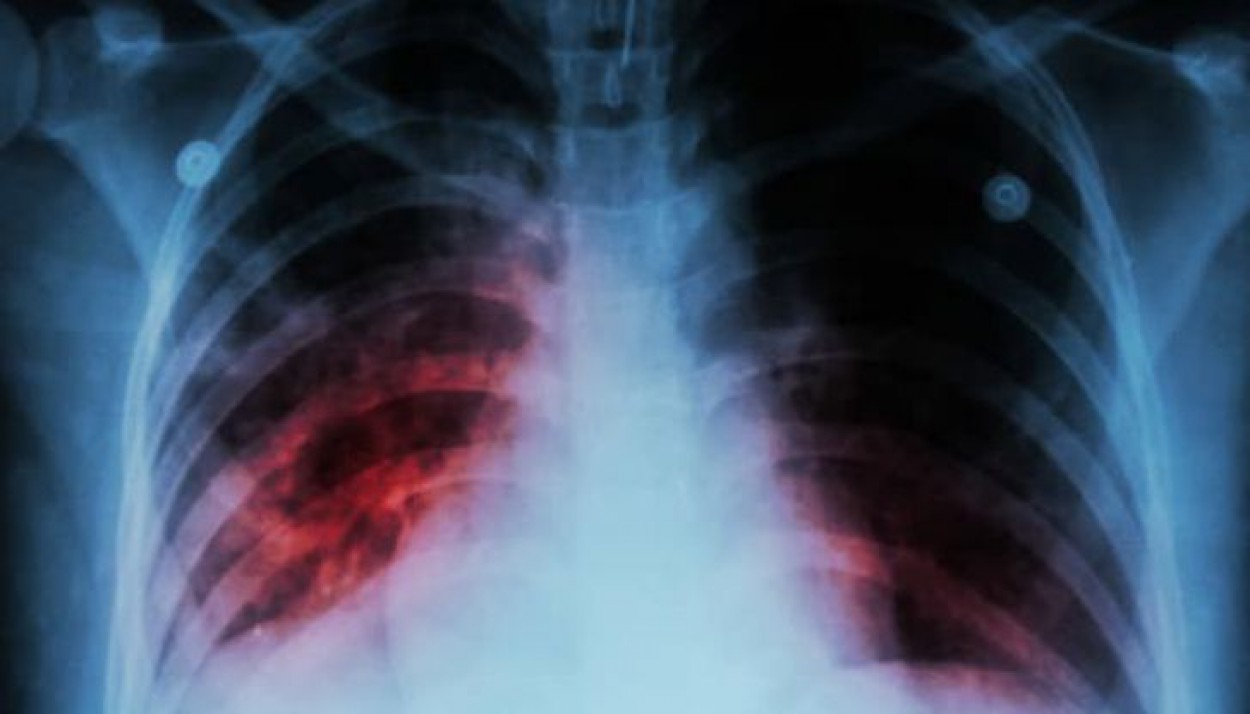

NVSC Kauno departamento specialistai primena, kad pagrindinis tuberkuliozės užsikrėtimo šaltinis yra žmogus, kuris serga atvira plaučių tuberkuliozės forma. Tuberkuliozės bakterijos patenka į orą, kai plaučių tuberkulioze sergantis žmogus kalba, kosėja ar čiaudi. Bakterijos ore gali išlikti kelias valandas, priklausomai nuo aplinkos sąlygų. Žmogus, įkvėpęs bakterijomis užteršto oro, gali užsikrėsti. Užsikrėtę asmenys savo organizme turi tuberkuliozės bakterijų, bet daugumai jos nėra aktyvios ir nesukelia ligos, nepasireiškia tuberkuliozei būdingi požymiai ir žmogus neplatina ligos sukėlėjo. Nustatyta, kad tik dalis užsikrėtusių asmenų (5-10 proc.) gali susirgti arba suserga tuberkulioze.

Tuberkuliozės simptomai pasireiškia, kai tuberkuliozės bakterijos žmogaus organizme tampa aktyvios, t. y. pradeda daugintis.

Pagrindiniai tuberkuliozės simptomai, kuriuos pajutus reikėtų kreiptis į savo šeimos gydytoją:

⦁ kosulys, trunkantis 3 ar daugiau savaičių;

⦁ kosėjimas su skrepliais ar su krauju.